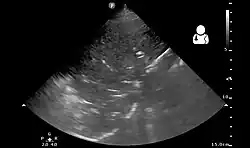

Lung ultrasound may also be useful in helping to make the diagnosis.[67] Ultrasound is radiation free and can be done at bedside. However, ultrasound requires specific skills to operate the machine and interpret the findings.[33] It may be more accurate than chest X-ray.[68]